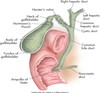

anatomy of gallbladder image

GB & biliary sysem

normal relational anatomy image

GB anatomy image